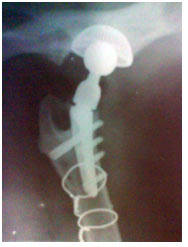

1a. Gambaran ventrodorsal persendian pinggul yang menderita Osteoarthritis parah.

1b. Gambaran ventrodorsal persendian pinggul yang menderita Osteoarthritis fase akhir.

2. Gambaran radiologi ventrodorsal gambar 1.